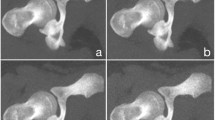

Using raw data from CT torsion measurements of the lower extremity, ULD-CT simulations were generated with the dedicated software package ReconCT (Version 14.2.0.40998, Siemens Healthineers) [18, 19]. Simulations were made at 10%, 5%, and 1% dose levels and compared to the original data sets (100% dose level). The software ReconCT essentially generates images with reduced radiation dose by adding noise to the raw data prior to the reconstruction process. Axial reformats (3-mm slice thickness; sharp edge–enhancing reconstruction Kernel B60; window center 450/width 1500) at every dose level were made twice using two different methods of raw data reconstruction: standard filtered back projection (FBP) and advanced modeled iterative reconstruction (ADMIRE Stage 5, Siemens Healthineers) (Fig. 1). Iterative reconstruction was used at the highest possible stage (stage 5) in order to achieve maximum possible noise reduction at the cost of slightly increased image blurring and reduced visibility of detail (but not necessary for delineation of cortical outline of bone).

A 17-year-old patient who received a preoperative CT torsion measurement of the lower limb; separately shown are the hip, knee, and ankle regions. Simulated ULD-CT data sets are shown with radiation dose of 10% (b), 5% (c), and 1% (d) of the original dose as well as the original CT data set with 100% radiation dose (a). Iterative reconstruction (ADMIRE) was used in the left column; filtered back projection (FBP) in the right column (e-h)